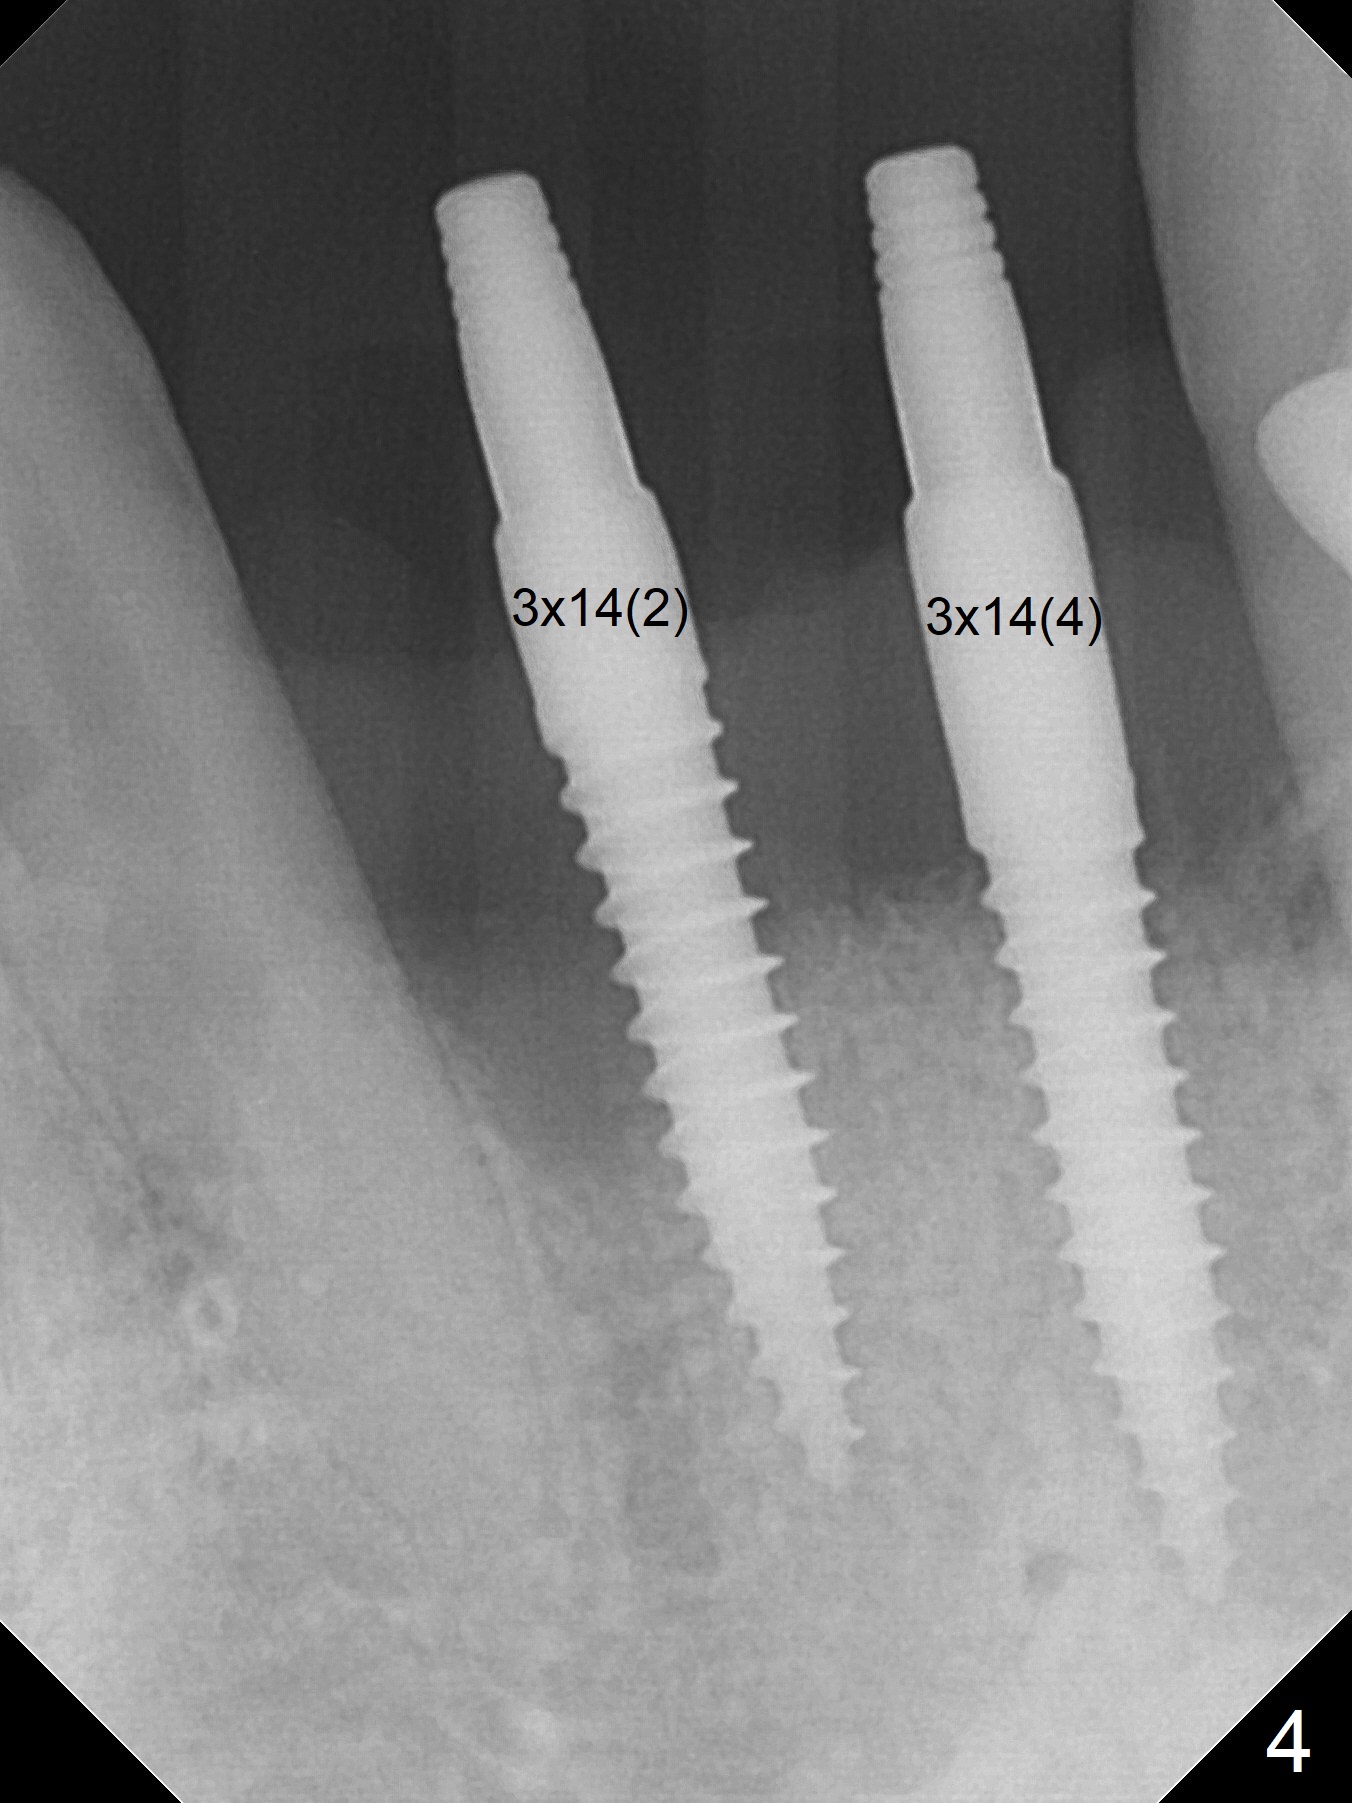

After extraction of 4 of the lower incisors, there are basically 2 sockets (#23/24 and 25/26), separated by the apparently midline bone (Fig.1 red line). In spite of using Lindamann bur to move the 25/26 osteotomy mesially, a 3x14(2) mm dummy implant remains close to the tooth #27 (Fig.2). The terminal branch of the Incisive Canal (<) is located between the lateral and central incisors. A de novo osteotomy (Fig.3 (1.5 mm drill)) is made mesial to the original one (O). While the 3x14(2) mm dummy implant is incompletely placed at #25/26, a 3x14(4) mm 1-piece one is placed at #23/24 (Fig.4). Finally the same implant is placed at #25/26 with placement of mineralized cortical/cancellous bone (Fig.5 *). When the large sockets are sutured, the supraerupted teeth #7-9 touch the lower gingiva (Fig.6). The incisal edge is reduced for clearance (Fig.7). Periodontal dressing is less likely to be dislodged with the incisal edge reduction (Fig.8,9). A provisional FPD is fabricated 1 week postop. Hard (Fig.10) and soft (Fig.11,12) tissues heal 5.5 months postop. The patient returns for crown cementation 3 months post impression (9 months postop, Fig.13,14).